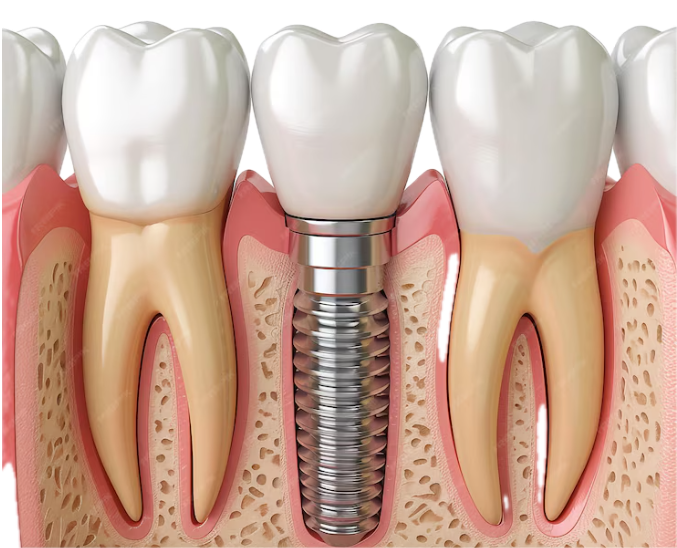

Вживленные импланты можно 114 фото